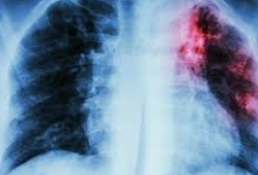

- 흉부 X-선 검사: 폐 내부의 결핵 병변을 확인하는 데 사용됩니다.

- 흉부 CT 검사: 필요시, 보다 정밀한 검사를 위해 시행됩니다.

- 정기적인 검사: 치료 중에는 정기적으로 객담 검사와 흉부 X-선 검사를 통해 치료 효과를 모니터링합니다.